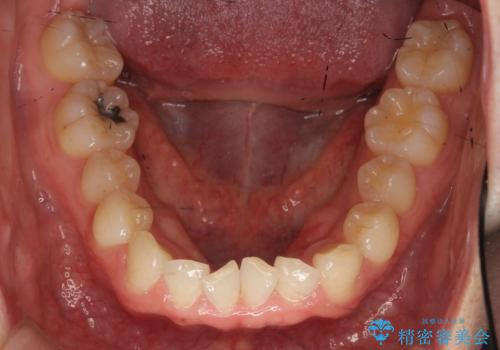

引っ込んだ前歯を並べる 歯を抜かないマウスピース矯正

- 右上の前歯が内側に入っているのを気にして来院。

右上の奥歯を後ろに移動して、前に出すスペースを確保してから並べました。

前歯が内側に入っていると、笑った時にそこが黒くなり、歯が抜けたように見えます。

口を開けたとき、笑顔の印象が大きく変わり、大変喜んでいただけました。